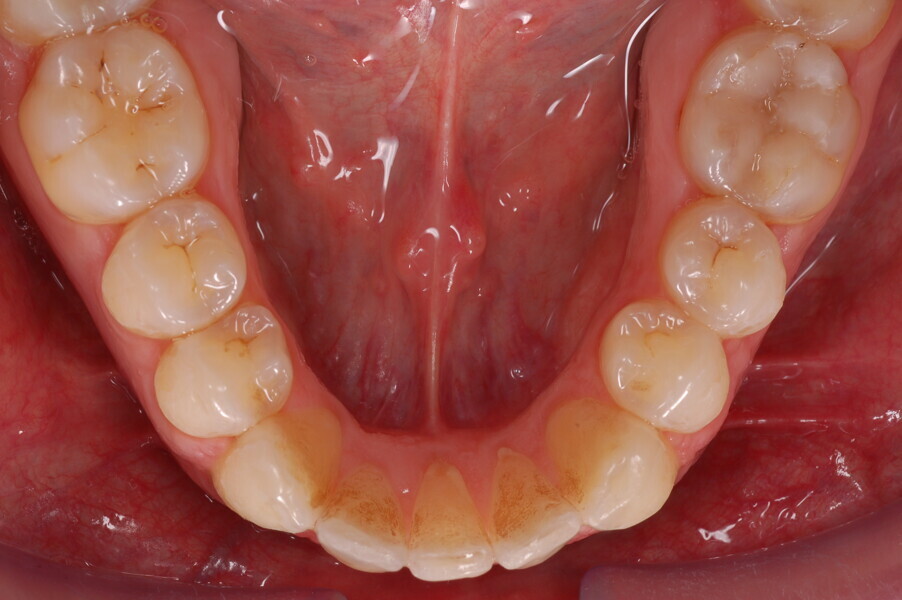

Figs. 1–8: Pretreatment facial and intra-oral photographs.

From the periodontal point of view, the patient showed a good attitude to oral hygiene, but crowding of the mandibular incisors made cleaning difficult in that area, causing plaque accumulation and localised gingival inflammation. The panoramic radiograph revealed the presence of the mandibular third molars and confirmed the absence of the mandibular right central incisor (Fig. 10).

The cephalometric analysis showed a skeletal Class II malocclusion (convexity of Point A: 4.9 mm), a slightly retruded chin position (facial depth: 78.1°) and a skeletal open bite tendency (lower facial height: 53.19°; facial axis: 80.58°; Fig. 9). The mandibular incisors were lingually tipped (Li–APog: 9.3°) and retruded (Li–APog: 1.55 mm), and there was an increased inter-incisal angle of 142.9°.